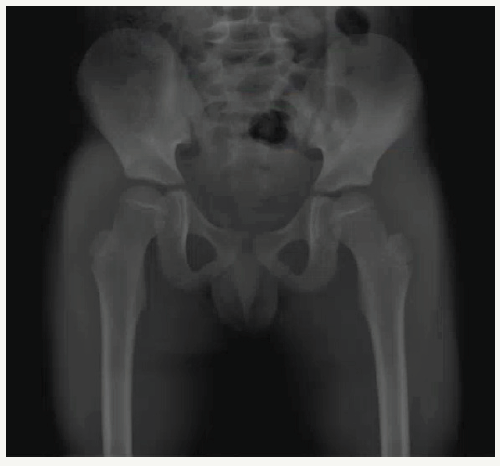

Figure 2: AP pelvis x-ray shows concentric anatomic reduction.

AP pelvis x-rays are needed after every closed reduction. Even in successful procedures, post-reduction x-rays may show asymmetrical hip joint widening compared to the other side.

Radiographic joint widening can be caused by intra-articular bone fragments (not always visible on x-ray), soft tissue interposition such as mentioned above, or even simple hemarthrosis. Some studies suggest a routine drainage of hip hemarthrosis after every dislocation, though this is not generally supported [7]. Mehlman et al. [2] suggested computed tomography (CT) if hip joint asymmetry is ≥2mm (measured from the medial edge of the femoral head ossification center to the lateral aspect of the acetabular tear figure). Other authors suggest post-reduction CT if there is gross hip instability after reduction or if ipsilateral periarticular fractures are present [8]. CT might show the typical acetabular fleck sign, suggestive of posterior acetabular osteochondral injury [9] (Figure 2 & 3).